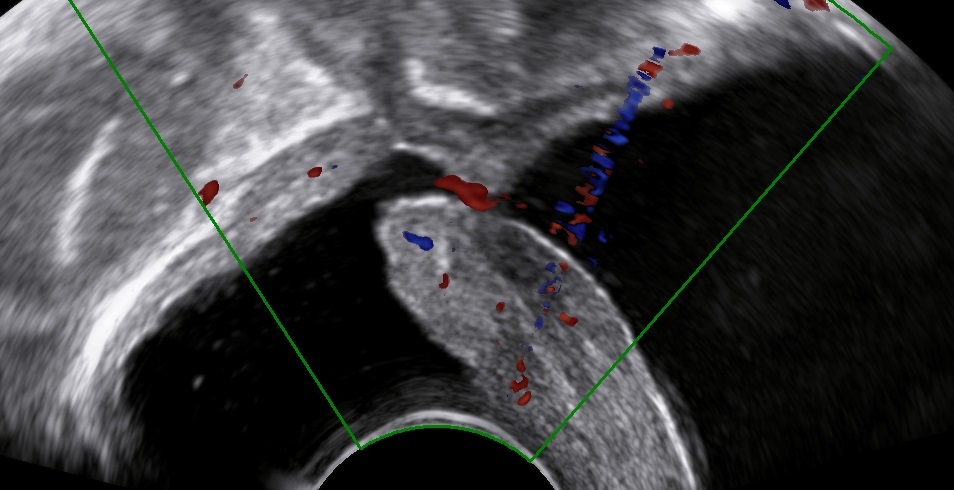

The following images and videos represent an abnormal passageway between the bladder and the vaginal apex following a complicated hysterectomy.